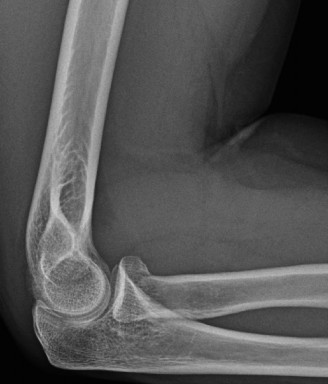

Understand common complications associated with performing surgery for scapulothoracic bursitis? CASE 33 A 42-year-old female presents to the office for follow up after sustaining a minimally displaced radial head fracture 3 months prior. She states she was initially treated in long-arm splint by the ER and did not follow up with an orthopaedic surgeon until now. Per her report, she removed the splint 4 weeks after the injury, but did not move her elbow due to pain. She now has no pain but is unable to reach that hand to her face or head. The remaining history is significant for previous ulnar nerve surgery for which she is unable to provide details. On physical examination, her upper extremity is normal except for limited flexion/extension, measured to be 80 to 50 degrees by goniometer. In addition, she has a well-healed surgical incision about the medial elbow, consistent with a previous surgery on her ulnar nerve. Her images are shown (Figs. 2–82 to 2–84).

Figure 2–82

Figure 2–83

Figure 2–84

What is the diagnosis?

The correct answer is (A). Classification of post-traumatic elbow stiffness allows for better understanding of the disease and allows the clinician to treat the underlying cause of the joint contracture. Intrinsic causes include: any problem within the joint such as incongruency, loose bodies, or severe osteoarthritis. Extrinsic causes include capsular tightness, muscle contracture, heterotopic ossification, and skin contractures. Early is defined as within 6 months of the injury while late is considered to be greater than 6 months after the injury. Patients that present in the early time frame have a significantly better chance at having a good result both from nonoperative and operative treatment.